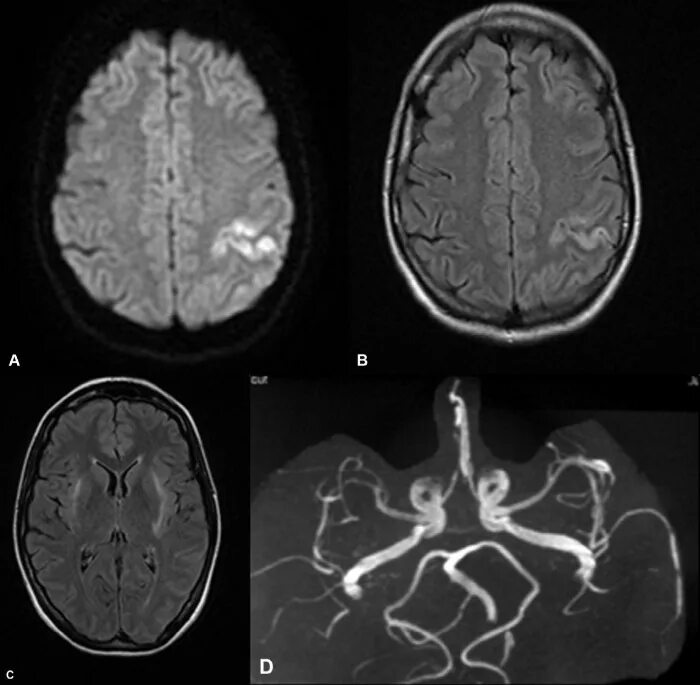

Субарахноидальное пространство лобных долей